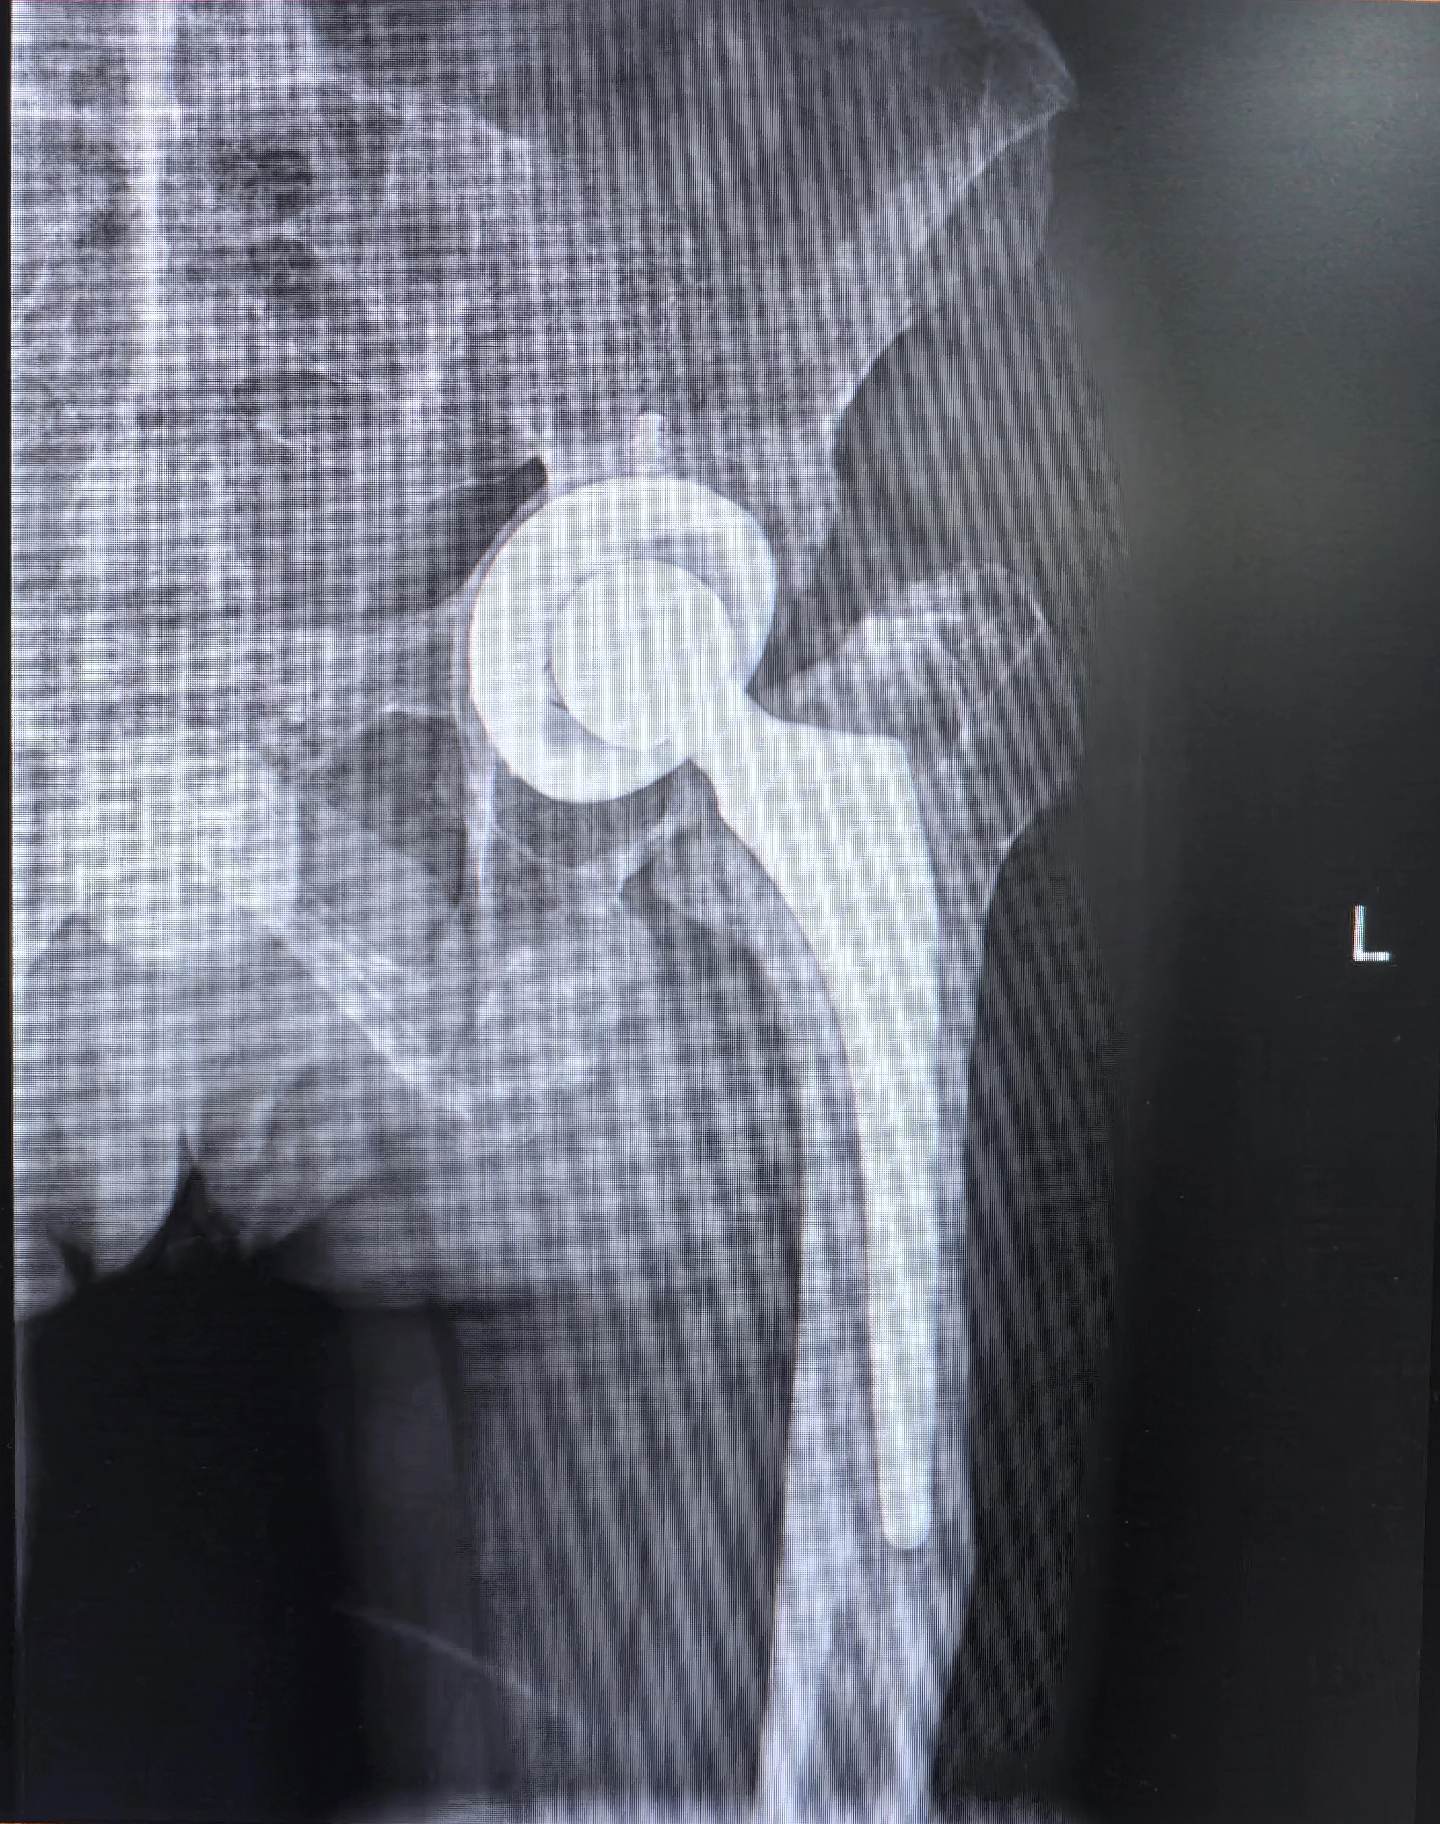

髋关节翻修。强脊炎THA后假体松动,术前短3cm,术后等长。难点:松动的股骨柄远端硬化如何突破?实际操作起来真的不容易。此例虽有插曲,好在医院大平台器械完备,结局满意,术后2天正常下床走路🌹